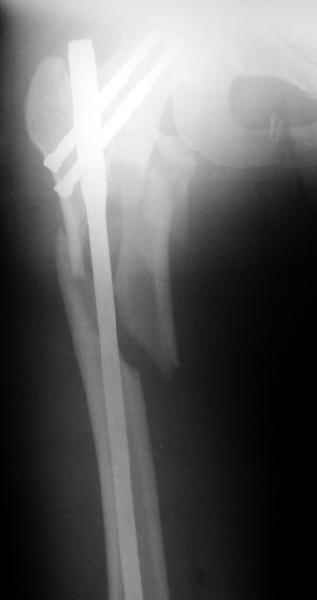

Другое наблюдение:Мужчина, 1957 г.р. Травма в результате ДТП 12.09.04г.

Диагноз: Закрытый оскольчатый подвертельный перелом правой бедренной кости со смещением отломков, оскольчатый перелом большого вертела, отрывной перелом малого вертела.Сопутствующие заболевания: Язвенная болезнь желудка, ремиссия.

Наверно, можно и так сказать, но можно и тоже самое - 4-фрагментный вертельный перелом. Выбор тот же, но с учетом молодого возраста реконструкционный гвоздь тут более применим. Вот уже наш пример.

Перелом подвертельный. Лечение оперативное, срочное,

PFN с длинной ножкой чтобы избежать стрессовые изменения в будущем. Обычно у молодых людей требуется проводить рассверливание канала как при гвоздевании.

В данной ситуации я бы провел остеосинтез при использовании длинного Gamma Nail